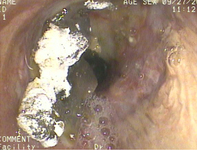

Бронхоскопия, показывающая аспирацию бария у пациента с трансплантацией легкого в правом главном бронхе после исследования с глотанием бариевой суспензии

Из коллекции д-ра Kamran Mahmood